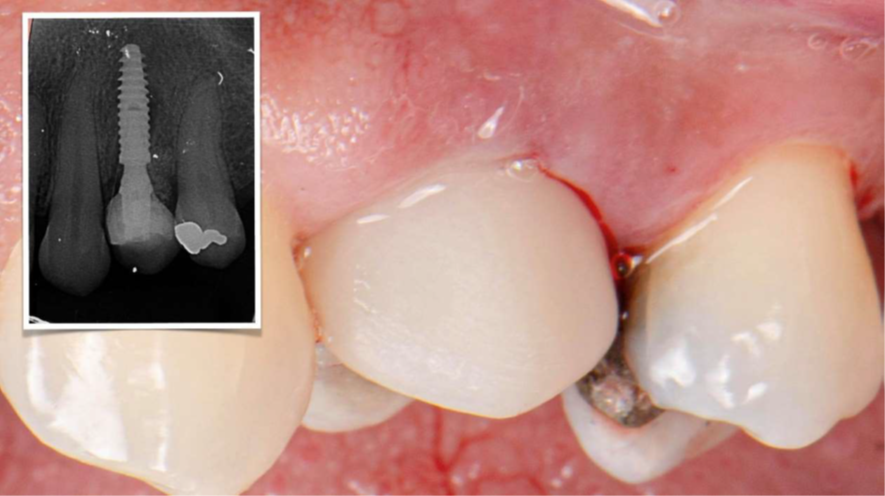

Fase protética digital — zircônia monolítica em fluxo CAD/CAM

Após cerca de 120 dias em função, com perfil gengival consolidado, realizou-se escaneamento intraoral com transferente digital específico sobre o pilar Ideale. O fluxo digital eliminou moldagens analógicas, reduziu etapas e possibilitou desenho preciso do perfil restaurador.

A coroa definitiva foi fresada em zircônia monolítica maquiada, material estável, resistente e com baixa porosidade. Com resistência flexural entre 900–1200 MPa, permite restaurações finas com segurança mecânica e excelente longevidade clínica. A prótese foi parafusada diretamente sobre o pilar Ideale, utilizando o parafuso Torx com torque recomendado de 20 Ncm. O parafuso Torx apresenta tamanho menor em comparação ao parafuso convencional, o que otimiza o espaço interno disponível — especialmente relevante em regiões anteriores ou coroas com menor espessura oclusal. Sua geometria permite maior eficiência na transmissão de torque com menor risco de espanar, além de melhor acoplamento chave/parafuso, conferindo segurança durante a instalação e remoção. A instalação direta sobre o Ideale reduz interfaces, microgaps e micromovimentos, favorecendo selamento marginal mais previsível e estabilidade dos tecidos ao longo do tempo.